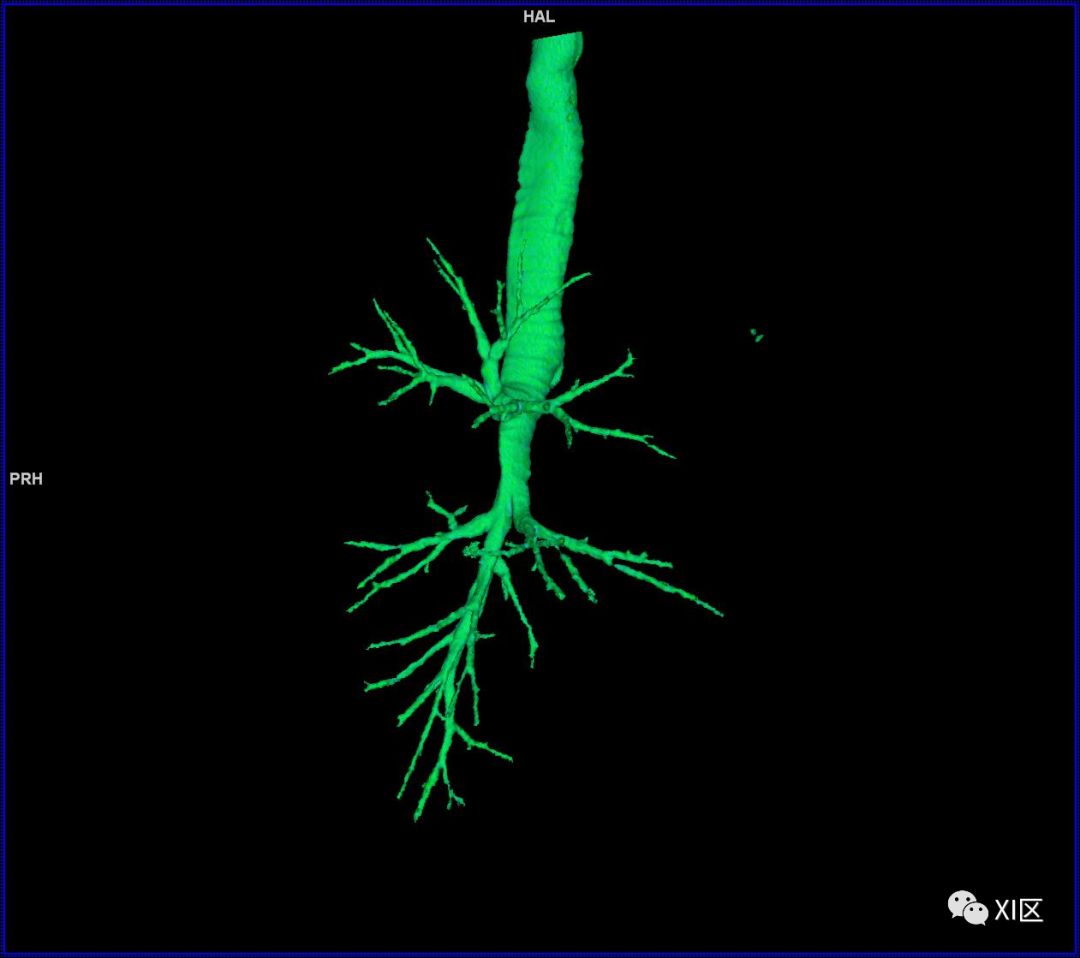

气管支气管树与两肺融合显示

气管树的解剖

人的支气管(第1级)至肺泡约有24级分支。支气管经肺门入肺,分为叶支气管(第2级),右肺3支,左肺2支。叶支气管分为段支气管(第3~4级),左肺8支、右肺10支。段支气管就是肺的分段的依据。段支气管反复分支为小支气管(第5~10级),继而再分支为细支气管(第11~13级),细支气管又分支为终末细支气管(第14~16级)。从叶支气管至终末细支气管为肺内的导气部。终末细支气管以下的分支为肺的呼吸部,包括呼吸细支气管(第17~19级)、肺泡管(第20~22级)、肺泡囊(第23级)和肺泡(第24级)。

气管支气管形如树状,因此也称气管支气管树。

气管树